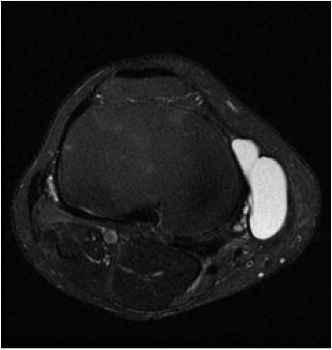

MRI

Meniscal tear + associated lateral meniscal cyst